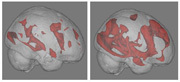

機能的MRIによる脳の活動状態

(赤い部分は活動状態を表す)

(左)読書中、(右)インターネット検索中

ウェブ検索をすることで中高年者の脳の機能が改善するかもしれないという研究結果が報告された。この研究では,インターネットで検索をしたことがある中高年者と,したことのない中高年者,合計24人に読書とウェブ検索をさせ,同時に脳の活動を機能的MRIで測定した。その結果,読書中では全員の脳に言語や記憶,視覚をコントロールする部分の活動がみられたが,ウェブ検索中では過去に検索をしたことがある人の脳にだけ,意思決定や複雑な論理的思考に関わる部分の活動が認められた。これは,中高年になってもまだまだ脳が学習できることを示している。(吉田素子)